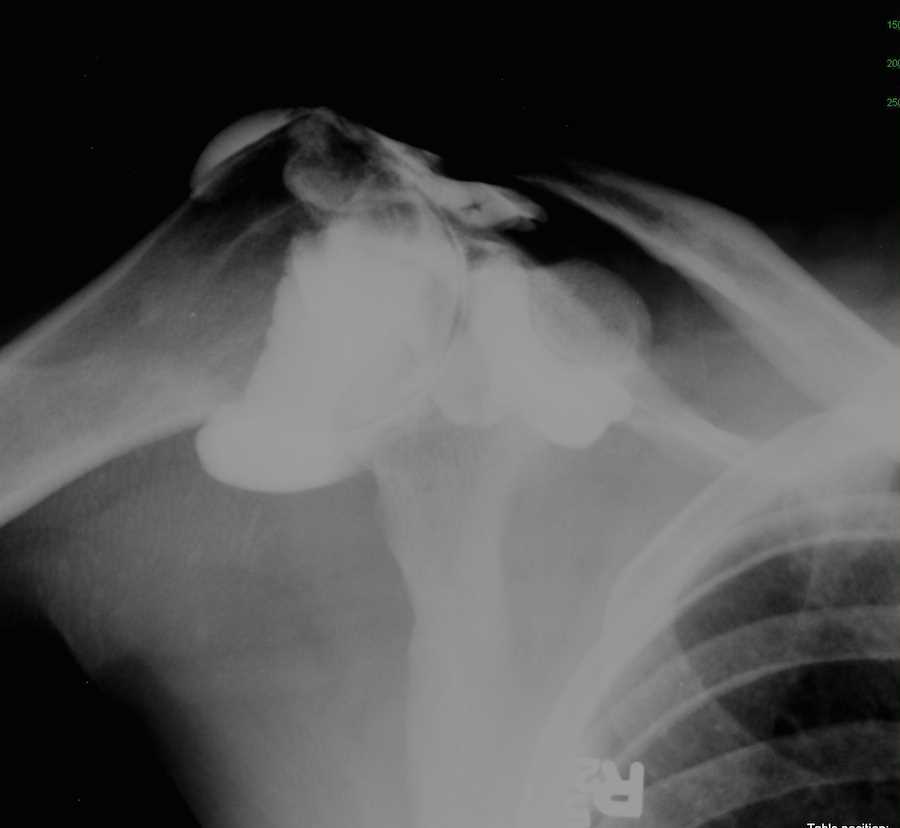

Small Bowel Obstruction on X-ray

Patient with severe of abdominal pain. Abdominal x-ray, flat and upright demonstrates air distention of the small bowel. On the upper right x-ray, small bubbles of air are seen in a “string of pearls” distribution which is characteristic of small bowel obstruction.